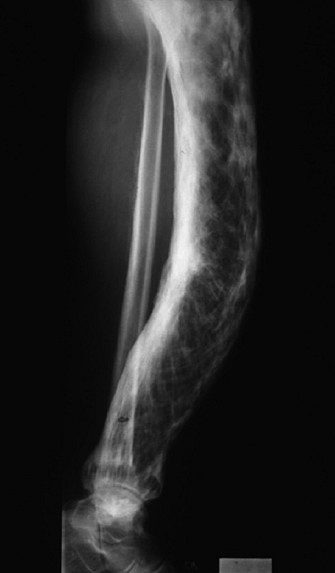

Les signes radiographiques sont habituellement assez caractéristiques pour affirmer le diagnostic (figure 1.8). Quelle que soit la localisation, le remaniement pagétique se traduit par :

– une atteinte plus souvent partielle que totale de la pièce osseuse ;

– une hypertrophie ou une déformation osseuse : l’os s’allonge, s’épaissit, prend un aspect massif ;

– une condensation osseuse trabéculaire, constituée de travées osseuses grossières, épaissies, dont l’orientation est anarchique ;

– une dédifférenciation corticomédullaire, estompant les limites entre la corticale et la médullaire de l’os.

Il est possible d’observer également :

– une zone d’ostéolyse, souvent à la jonction avec l’os sain, faisant craindre une dégénérescence sarcomateuse ou le développement d’une métastase osseuse en os pagétique ;

Fig. 1.8. Maladie de Paget. Aspect radiographique. Radiographie d’une forme évoluée d’atteinte pagétique du tibia montrant les lésions caractéristiques de l’ostéopathie : hypertrophie, déformation, lésions mixtes de résorption et de condensation, aspect fibrillaire de la trame, dédifférenciation corticomédullaire